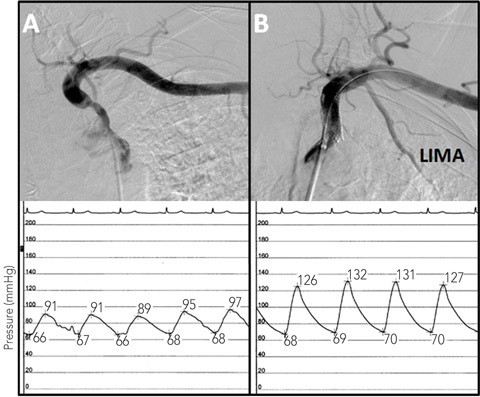

| 2: Angiograms of the left subclavian stenosis before (A) and after (B) stenting, showing the improvement in antegrade LIMA flow. The intra-arterial subclavian pressure tracings are shown below the angiograms. Before stenting (left) the pressure tracing is blunted, while after stenting (right), there is an improvement in blood pressure and normalisation of the arterial waveform. |